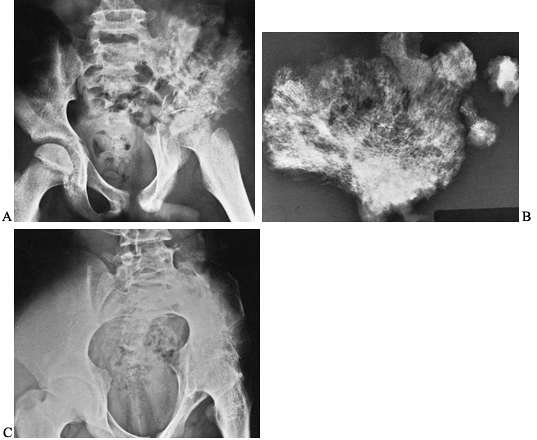

are most profound in the hip (Fig. 134.4).

![]() |

|

Figure 134.4. A 16-year-old patient developed severe pain in the left hip girdle and a temperature of 104°F (40°C). A: He developed osteomyelitis of the left iliac wing, as well as septic arthritis of the left hip joint. B: A sequestrectomy of the left ilium was performed and the wound was packed open. C:

The patient’s extremity was placed in a hip spica cast, which resulted in bony ankylosis of the left hip. (Note: This case is from 1939, the preantibiotic era). (Radiographs courtesy of Dr. Henry Jones, Radiology Department, Stanford University Medical Center.) |